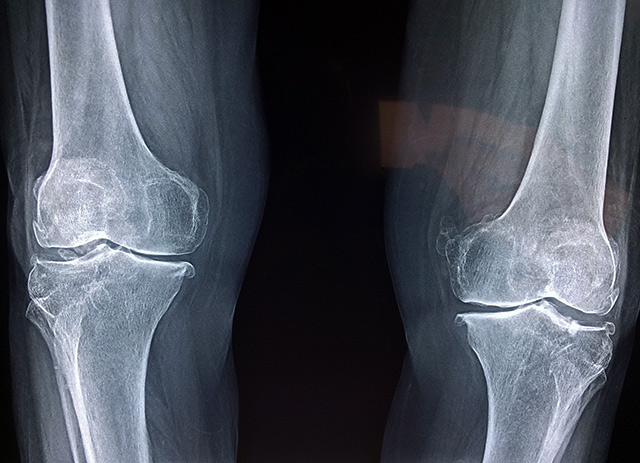

x-ray of the knees x-ray of the knees